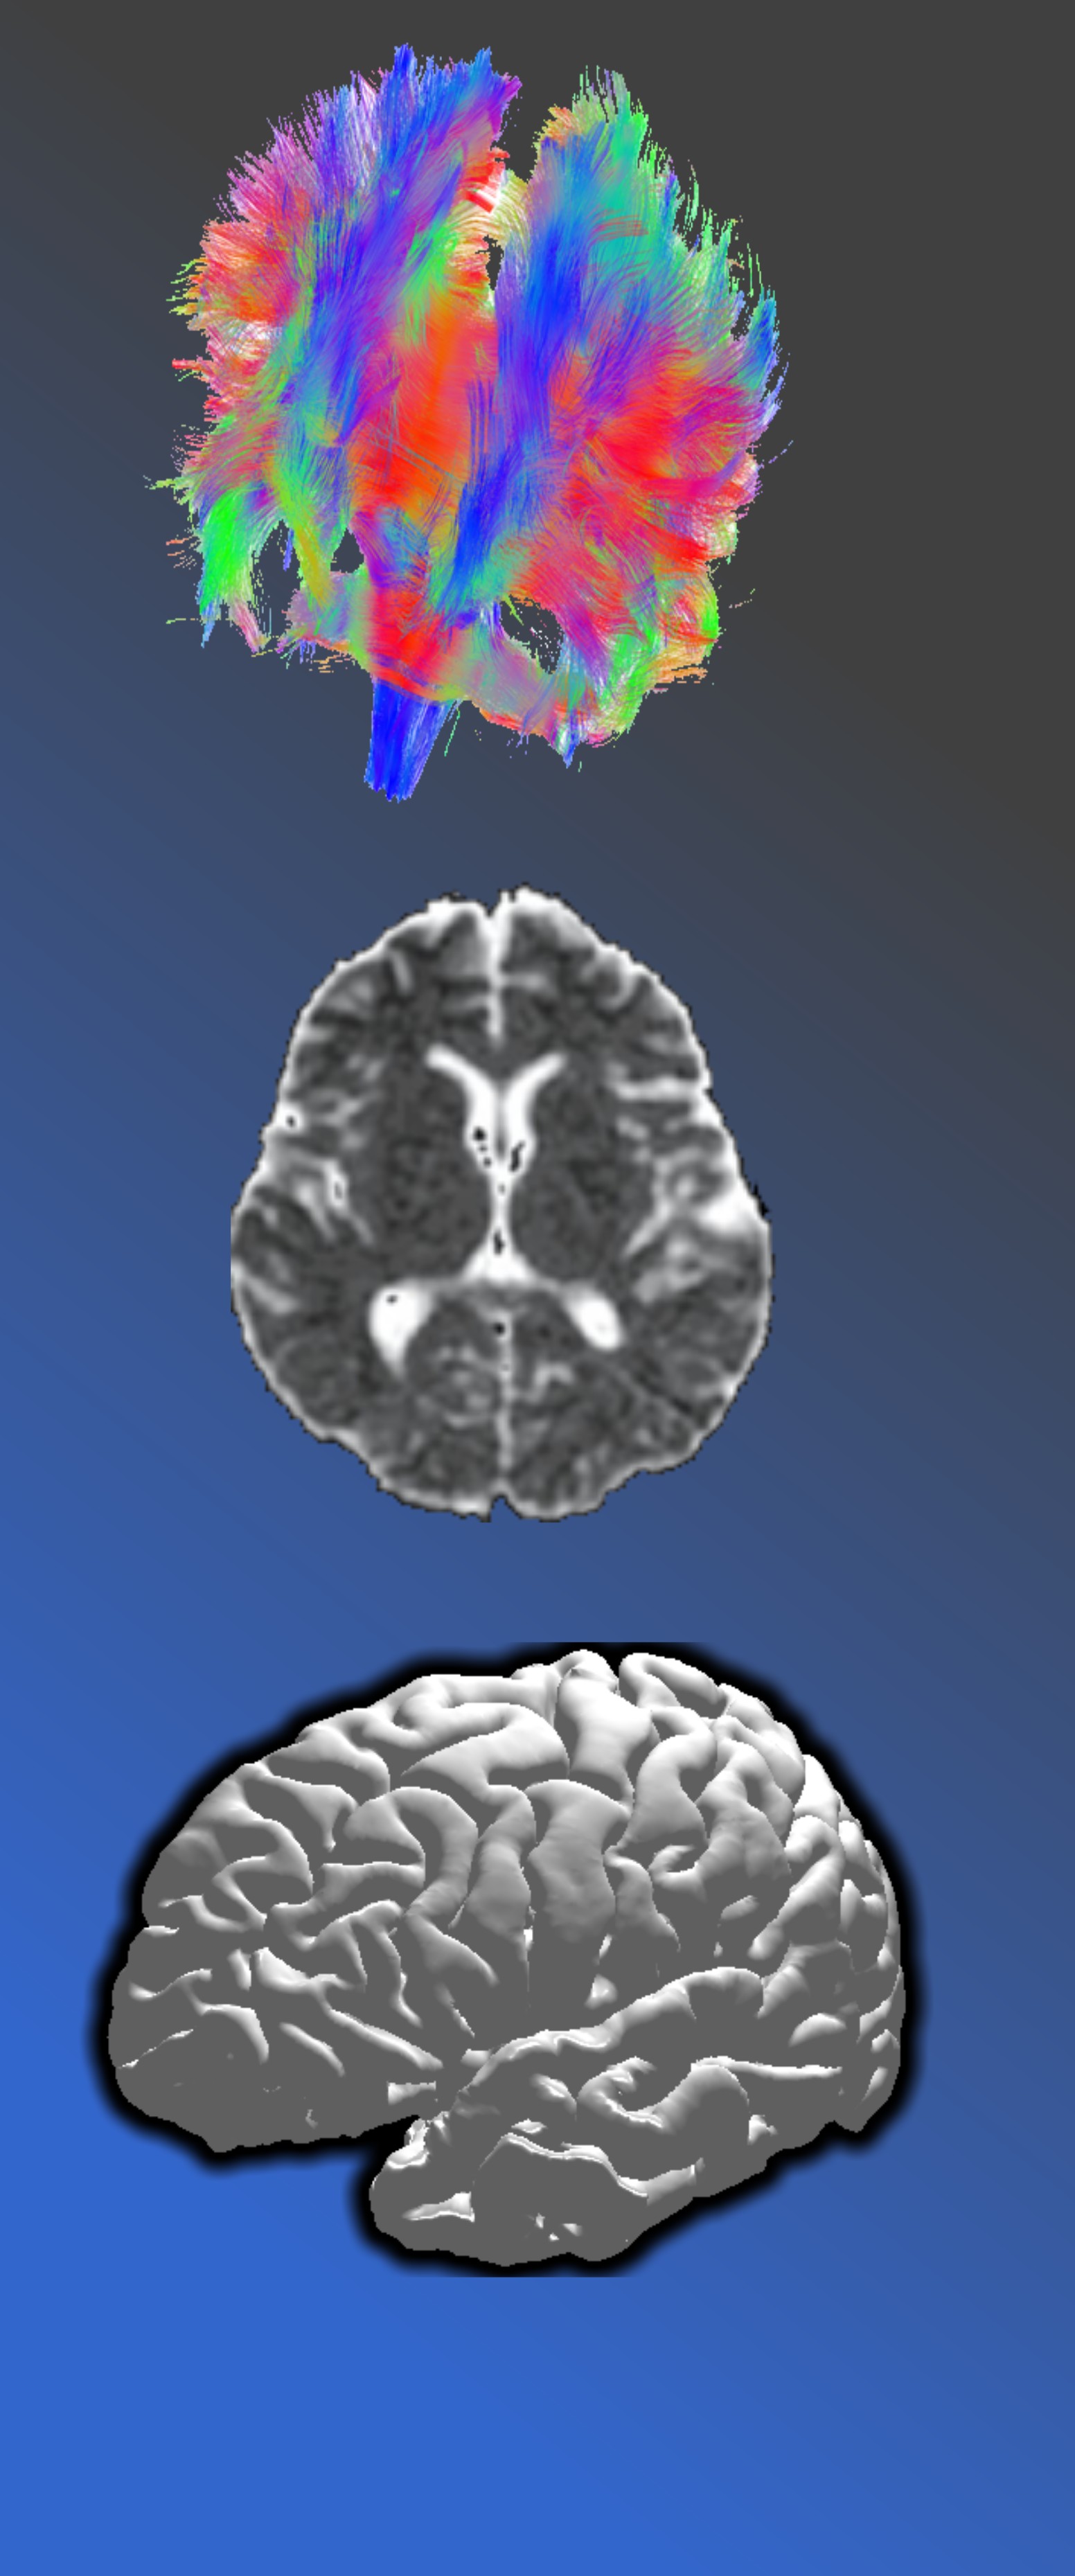

Циљ предмета је упознавање са принципима функционисања магнетно-резонантног имиџинга, различитим модалитетима добијања МРИ слике и МРИ техникама за добијање информација о анатомији и физиолошким процесима у живом организму.

Курикулум предмета укључује предавања о основама формирања МРИ слике, механизмима релаксације-спин-решетка и спин-спин релаксација, К-простору и његовим особинама, основним МРИ секвенцијама, дводимензионалној Фуријеовој трансформацији, параметрима аквизиције: времену понављања и времену еха, секвенцији инверзије опоравка магнетизације, градијент ехо секвенцијама, ехо-планарним секвенцијама. основним деловима МРИ хардвера, паралелном имиџингу, специјализованим МРИ секвенцијама, МР спектроскопији, дифузијски и перфузијски наглашеном МРИ. функционалном МРИ и сусцептибилношћу наглашеном МРИ.